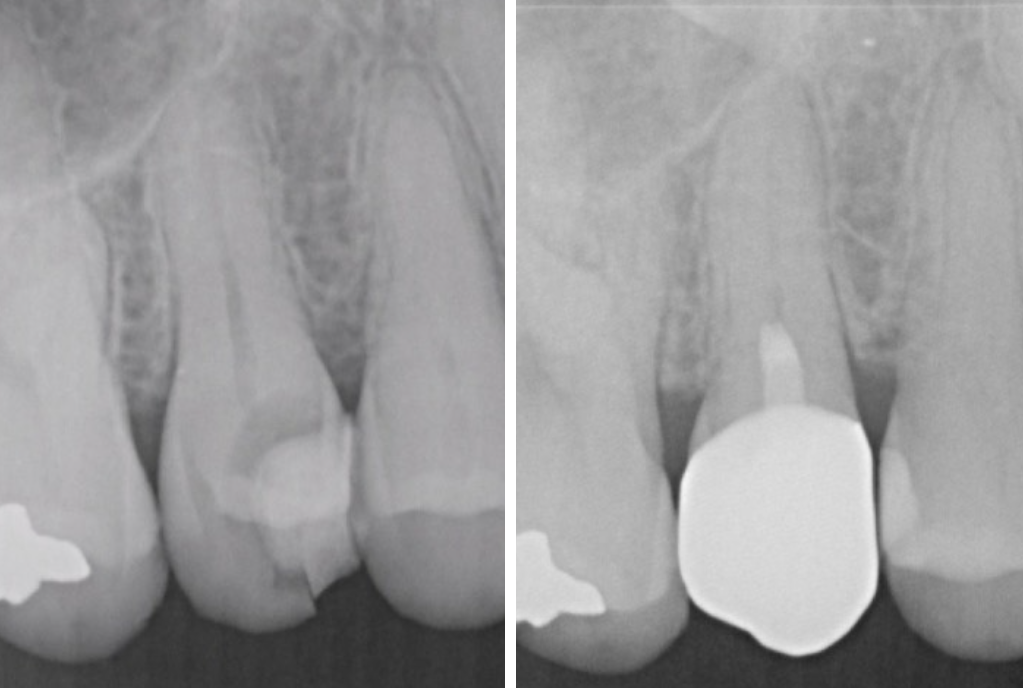

症例2

| 患者様データ | 30代 男性 |

| 来院時の主訴 | 「右上の歯が何もしなくても痛い。他院で神経を取ると言われたが、残せないか相談したい。(セカンドオピニオン)」 |

| 術前検査結果 | 歯髄の生活反応有り、自覚症状有り |

| 医院の診断 | 症候性可逆性歯髄炎 |

| 通院期間 | 1年間 |

| 来院回数 | 7回 |

| 治療費 | 総額:197,000円(税抜) 【内訳】 セカンドオピニオン20,000円、歯髄保存療法(MTA使用)55,000円、セラミック治療120,000円、術後経過観察時検査代1,000円×2回分 |

| リスクと副作用 | ①適応症が限られる ②時間が経過してからトラブルが生じることがあるため、長期的(約半年〜4年)な経過観察が必要 |

| ここがこだわりのポイント!☝ | 術前の症状の強さは神経を残せるかどうかには関係ありません。術前検査情報に加えて、術中のマイクロスコープでの歯髄診査にて神経を残せるかどうかの最終判断を行なっています。 |